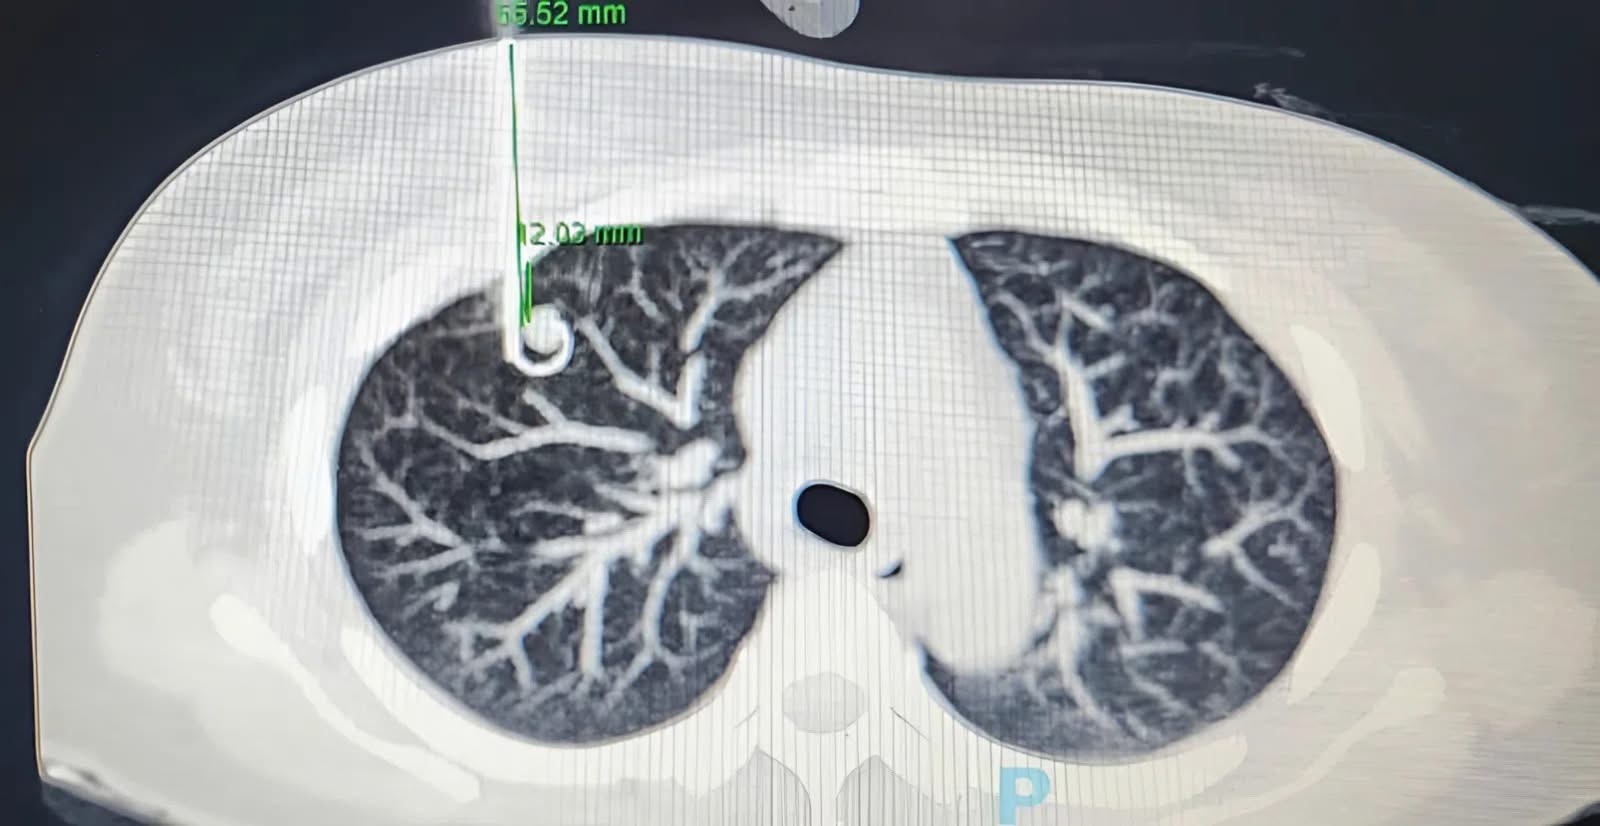

Một trong những trường hợp cụ thể là bệnh nhân N.T.K.C. (50 tuổi, TP.HCM) được phát hiện có nốt mờ 11 mm ở thùy trên phổi phải khi chụp CT ngực liều thấp khi đi tầm soát sức khỏe định kỳ tại bệnh viện Chợ Rẫy.

Trước kết quả đó, các bác sĩ tại khoa Ngoại lồng ngực bệnh viện Chợ Rẫy đã tiến hành định vị khối u phổi bằng kim trước phẫu thuật để xác định chính xác vị trí tổn thương. Sau đó, thực hiện phẫu thuật nội soi robot cắt thùy trên phổi phải, nạo hạch nhóm 2, 4, 7, 9, 10, 11. Sau 1 ngày được phẫu thuật, bệnh nhân C. hồi phục nhanh, rút dẫn lưu và xuất viện vào ngày thứ 4.